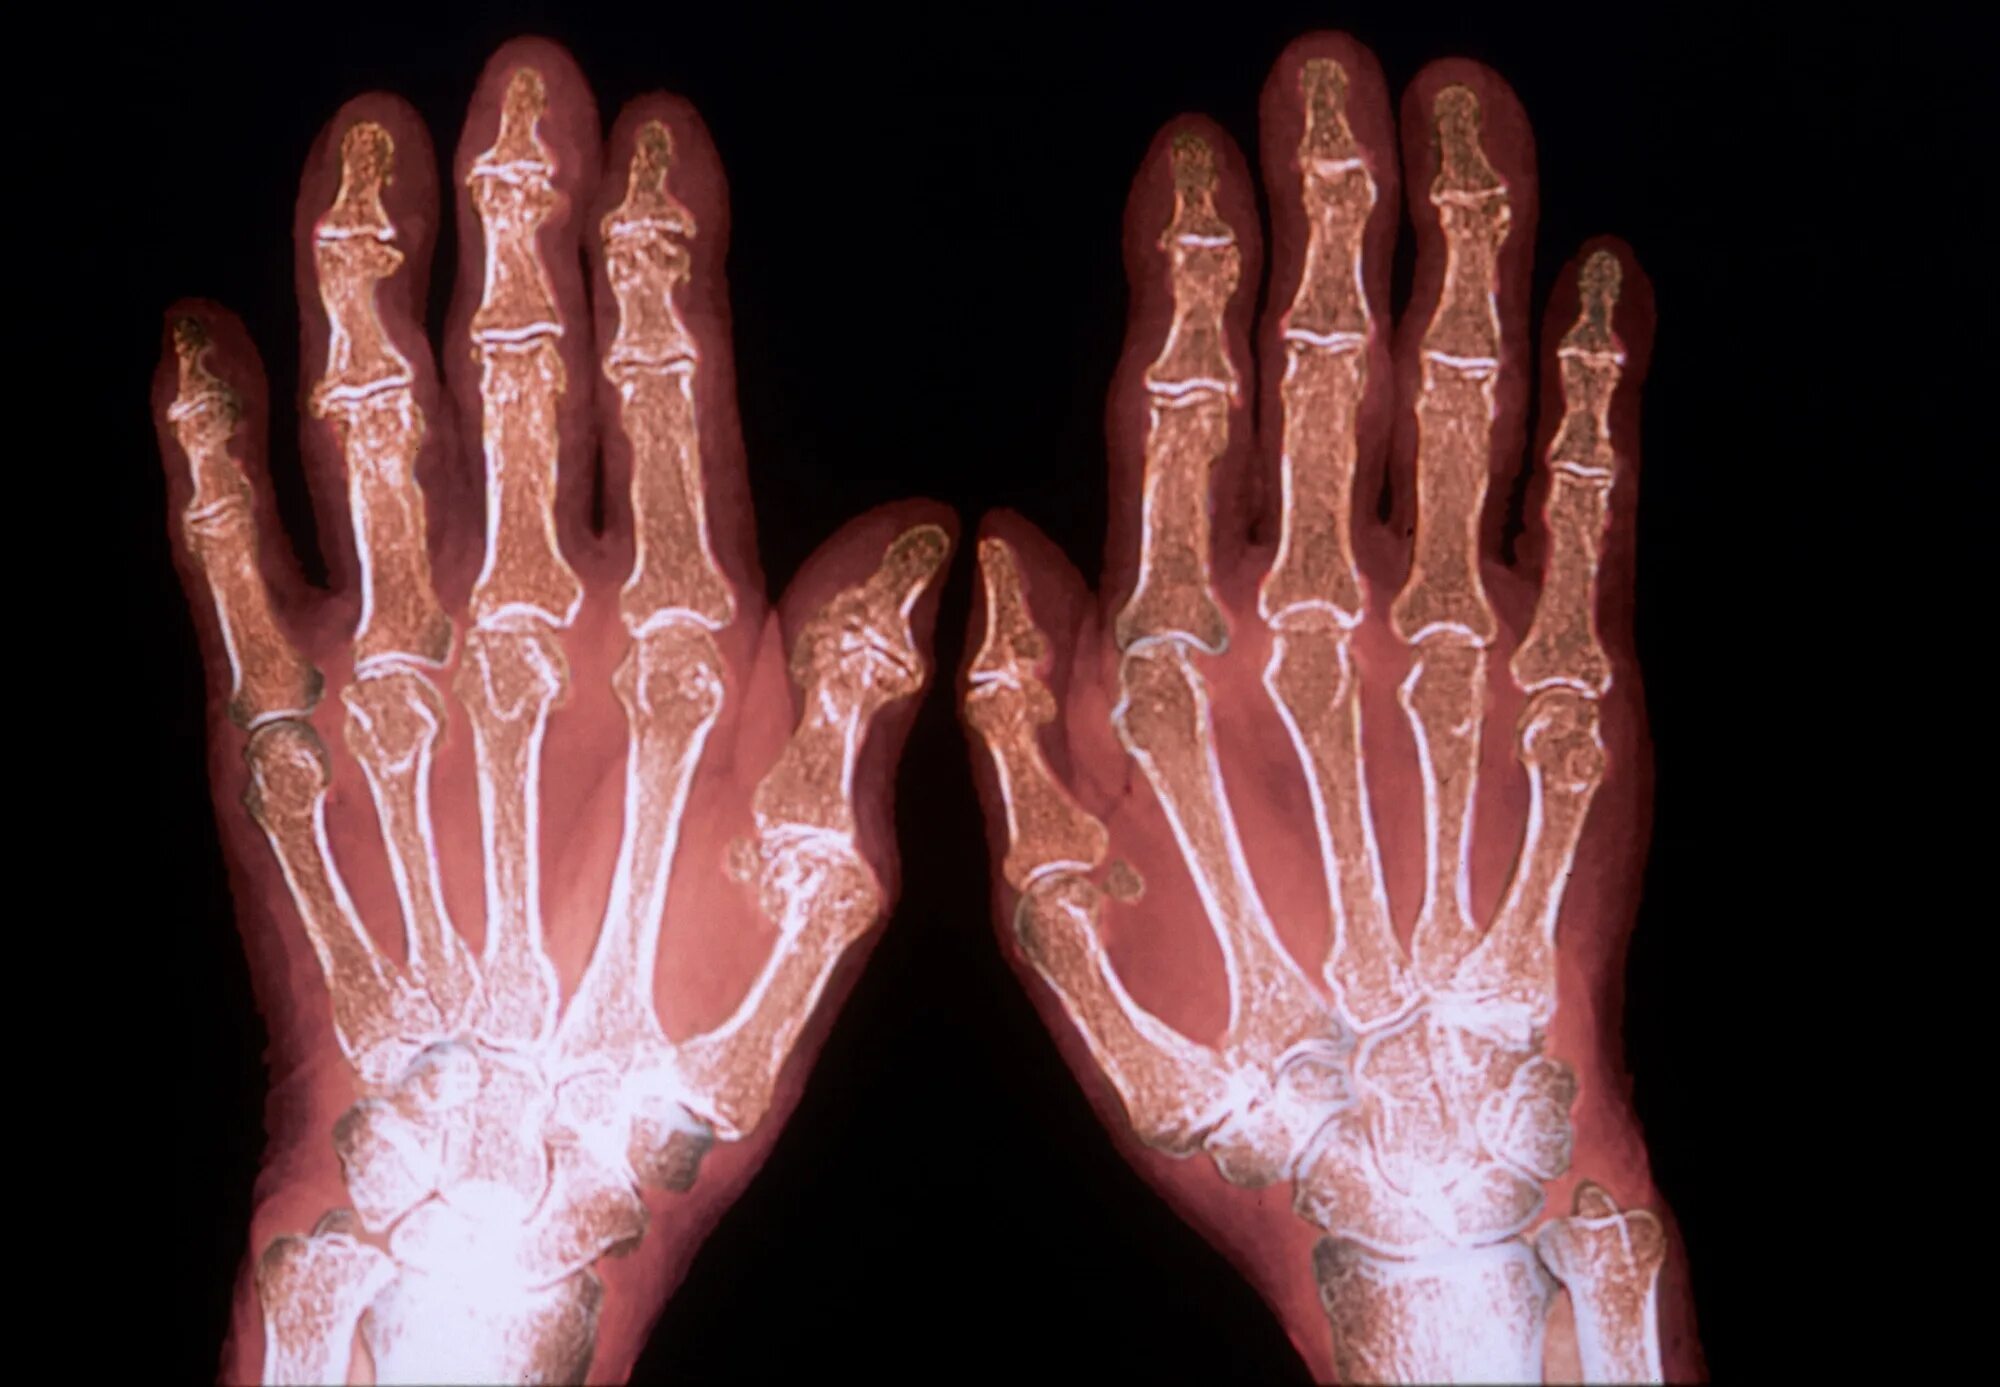

Артрит прогноз